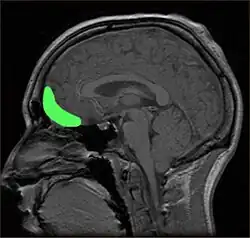

Zudem werden bildgebende Verfahren wie die Funktionelle Magnetresonanztomographie (fMRT) und Elektroenzephalographie (EEG) eingesetzt, um Gehirnstrukturen auszumachen, die spezifisch auf ästhetische Erfahrungen reagieren und daher als deren neuronale Grundlagen verstanden werden können.[3] Auch Untersuchungen des ästhetischen Empfindens von Patienten mit spezifischen Hirnstörungen wie dem Savant-Syndrom oder traumatischen Hirnverletzungen können für diesen Zweck eingesetzt werden.[4] Von besonderem Interesse sind auch die Werke von Künstlern mit derartigen Störungen.

Gehirnareale mit Bezug zu ästhetischer Wahrnehmung

Um ästhetische Wahrnehmung mit bestimmten Gehirnarealen in Verbindung zu bringen, werden bildgebende Verfahren wie fMRT, EEG oder MEG eingesetzt, meistens während die Probanden Kunstwerke betrachten.[14][15] Dabei wird die neuronale Aktivität zwischen verschiedenen Bedingungen verglichen, etwa zwischen dem rein „pragmatischen“ Betrachten und der Betrachtung unter künstlerischen Gesichtspunkten,[5] zwischen verschiedenen Kunststilen[16] oder zwischen als schön oder hässlich bewerteten Bildern[16][17] oder geometrischen Formen[18]. Die in einer bestimmten Bedingung besonders aktiven Hirnregionen werden dann dem jeweiligen Aspekt als zugehörig angesehen.

Die Ergebnisse dieser Studie weisen weniger auf eine klar umrissene Hirnregion hin, die spezifisch für Kunstempfinden wäre, sondern eher auf ein hierarchisches Netzwerk solcher Regionen.[14] Zunächst sind die visuellen Areale unterschiedlich aktiv, je nachdem welche Art von Gemälde betrachtet wurde (abstrakte oder gegenständliche Malerei, Stillleben, Landschaftsgemälde oder Porträts).[16][17] Die Beurteilung eines Bildes als schön ging häufig mit der Aktivierung frontaler Areale einher, etwa dem orbitofrontalen Cortex,[16][18] dem Cortex cingularis anterior[16][17] und dem dorsolateralen[19] und ventralen[18] präfrontalen Cortex. Speziell der orbitofrontale Cortex wird auch allgemeiner mit der Beurteilung des Belohnungswerts eines Reizes in Verbindung gebracht.[20]

Des Weiteren wurden Aktivierungen von Arealen beschrieben, die mit Emotionen in Verbindungen gebracht werden (Amygdala, Inselrinde). Cinzia Di Dio und Vittorio Gallese[15] betonen zudem die Bedeutung motorischer Areale wie dem Prämotorcortex und den posterioren parietalen Cortex, insbesondere bei der Betrachtung von Statuen, die bestimmte Bewegungsposen zeigen.[21]